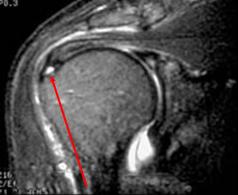

Partial rotator cuff tear

Intact outer

tendon fibers

Fluid in inferior part of

supraspinatus tendon